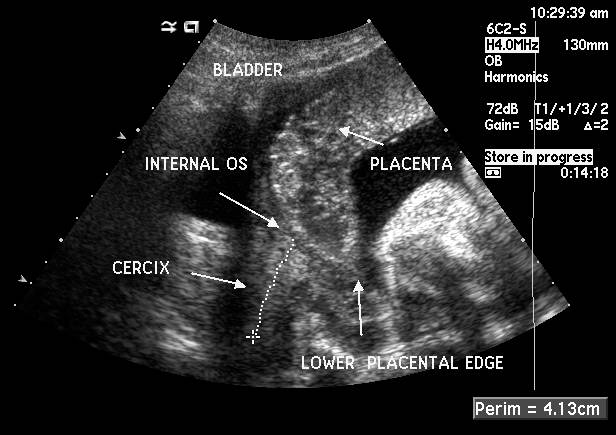

Placenta Previa

2. A condition of pregnancy in which the placenta is implanted abnormally in the uterus so that it impinges on or covers the internal os (opening) of the uterine cervix

2. Diagnosis

1. Ultrasound